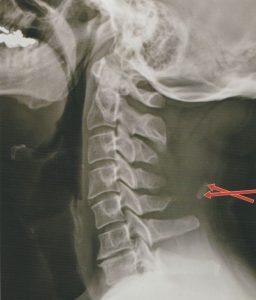

경추 항인대 석회화

경추 항인대 석회화 안녕하세요. 고래한의원 원장 박대명입니다. 오늘은 흔하게 접하는 질환은 아니지만, 발생하게 되면 목 움직임에 상당한 불편을 줄 수 있는 ‘경추 항인대 석회화’에 대해 이야기해 보겠습니다. ‘경추 항인대 석회화’는...